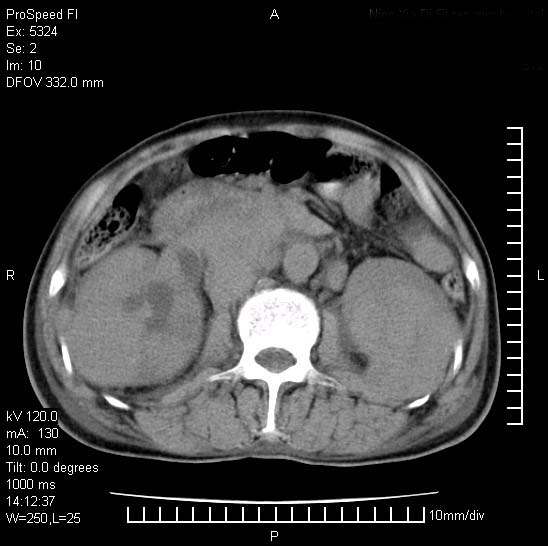

患者阴囊肿大14月,腰痛2个月,咳嗽,咳痰1周,患者现在肾功异常,做增强有些担心,我们用的是欧乃派克.

右侧肾癌伴腹膜后淋巴结转移!

右侧肾癌后腹膜转移,腹腔少量积液

腹膜后淋巴结肿大包饶腔静脉,双肾病变,建议增强

双肾均有软组织密度舯物,腹膜后淋巴结肿大包饶腔静脉------考虑为恶性占位病变,转移瘤可能。

1)考虑双肾恶性肿瘤(肾癌?)。2)腹膜后淋巴结肿大,多为肿瘤转移所致。

腹腔积液,双肾均有稍高密度肿块,主动脉旁广泛淋巴结肿大,融合,无显著肿块坏死征像,多考虑淋巴瘤累及双肾,不排除肾癌伴转移(肾癌这么大应该较多坏死了),另阴囊肿大,不知是实质肿大还是阴囊积液,如是是积液,多为腹腔肿块压近睾丸静脉所致,如是是实性的,多为淋巴瘤

1、淋巴瘤,双肾转移瘤;2、双侧肾癌,伴有腹膜后淋巴结转移。

双肾均有软组织肿块伴腹膜后淋巴结肿大融合,右侧结肠旁沟积液;考虑恶性肿瘤。转移瘤?淋巴瘤?

双肾增大,腹膜后多发肿大淋巴结影.首先考虑淋巴瘤.